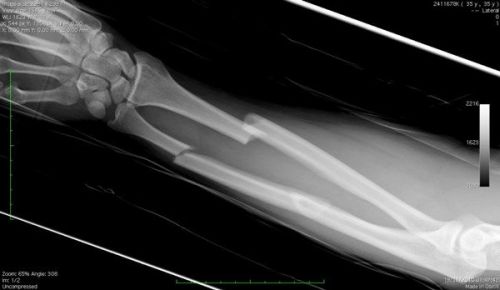

Рентген конечностей |

0,001 |

Менее 1 |

3,0 |

Как правило, количество таких процедур не должно превышать 1 раза в год. В отличие от диагностики внутренних органов, рентгенологическое исследование челюстной области и конечностей не представляет для детей серьезной опасности, поскольку для получения сведений о наличии перелома или причинах воспаления периодонта требуется незначительная доза излучения. Кроме того, современная аппаратура позволяет строго ограничивать зону облучения, а в некоторых случаях, предусматривает способы изолирования частей тела от рассеивающихся лучей свинцовыми фартуками.